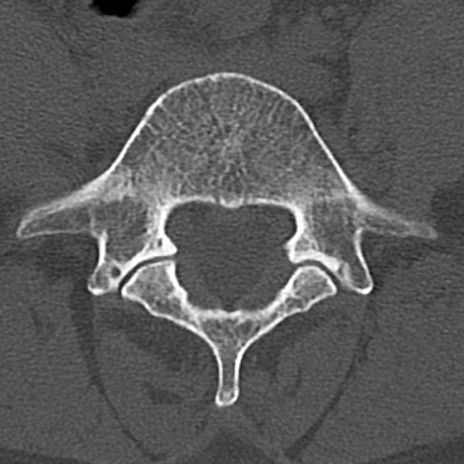

腰椎CT

横断像と矢状断像